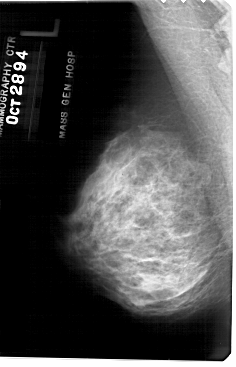

A_1781_1.LEFT_MLO

LEFT_MLO LINES 5491 PIXELS_PER_LINE 3526 BITS_PER_PIXEL 12 RESOLUTION 43.5 NON_OVERLAY